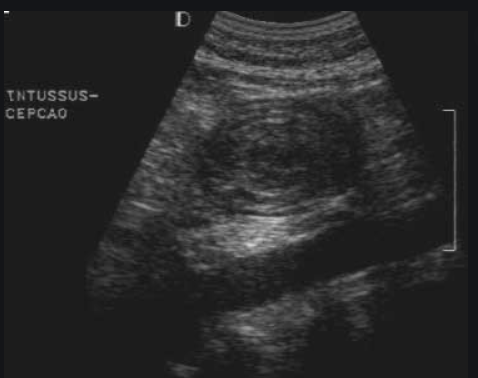

Como é feito o dx de II?

Clínico + exames complementares (USG abdominal é o de escolha - imagem tubular em pseudorrim no corte longitudinal e a imagem em alvo no corte transversal).